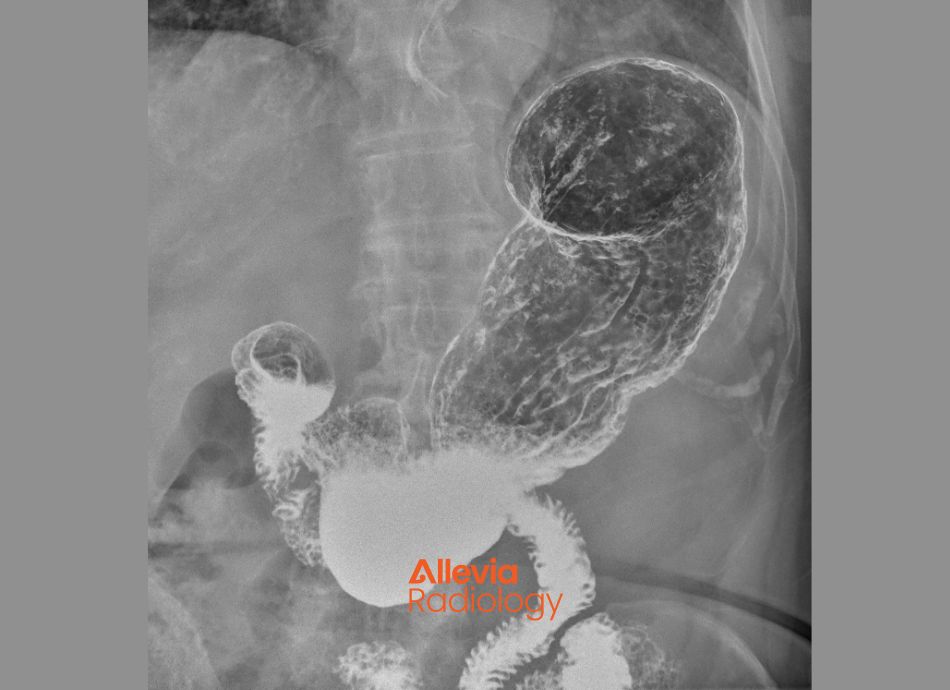

The image below is of a barium swallow.

X-ray image of a barium swallow in the oesophagus

Image credit: Canva